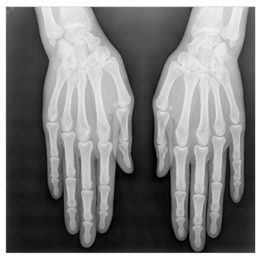

In this section, we present and analyze the results obtained with the proposed method, and compare it to methods proposed in similar works. The proposed watermarking system is implemented using MATLAB and executed on a Windows machine with the following characteristics: Intel R Core i5 processor, 4 GHz, 4 GB RAM, and Microsoft Windows 8 Professional operating system platform. In our experiments, we have used DICOM images of size 512 × 512 pixels as shown in Table 1.

Table 1.

Original images.